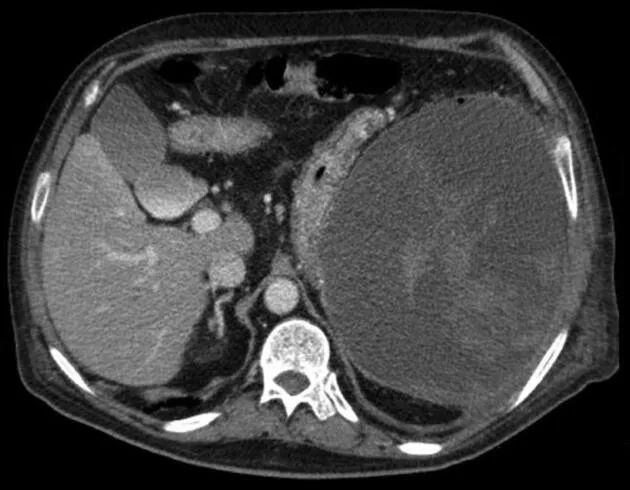

遂进行腹部CT扫描,发现隐藏的脾脏破裂,以及大的包膜下血肿,大小18*17*15 cm(图1),无活动性出血。

图1. 腹部CT扫描,显示脾脏破裂、大的包膜下血肿。